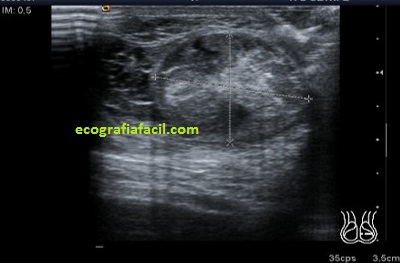

En algunas ocasiones podemos encontrarnos esto:

Compara la imagen 1 y la 2, grábala en tu memoria fotográfica. Ambas son unas imágenes en corte longitudinal del teste derecho de dos pacientes distintos.

Una vez que hemos encontrado la lesión, es momento de estudiarla detenidamente, su aspecto, tamaño bordes y vascularización son vitales para que la radióloga pueda efectuar un informe.

La imagen 3 y 4 son parte estudian en eje largo y corto las medidas de la lesión en los tres ejes del espacio, en ocasiones, podemos tener más de una lesión. Siempre super atentos si las lesiones son intra o extratesticulares.